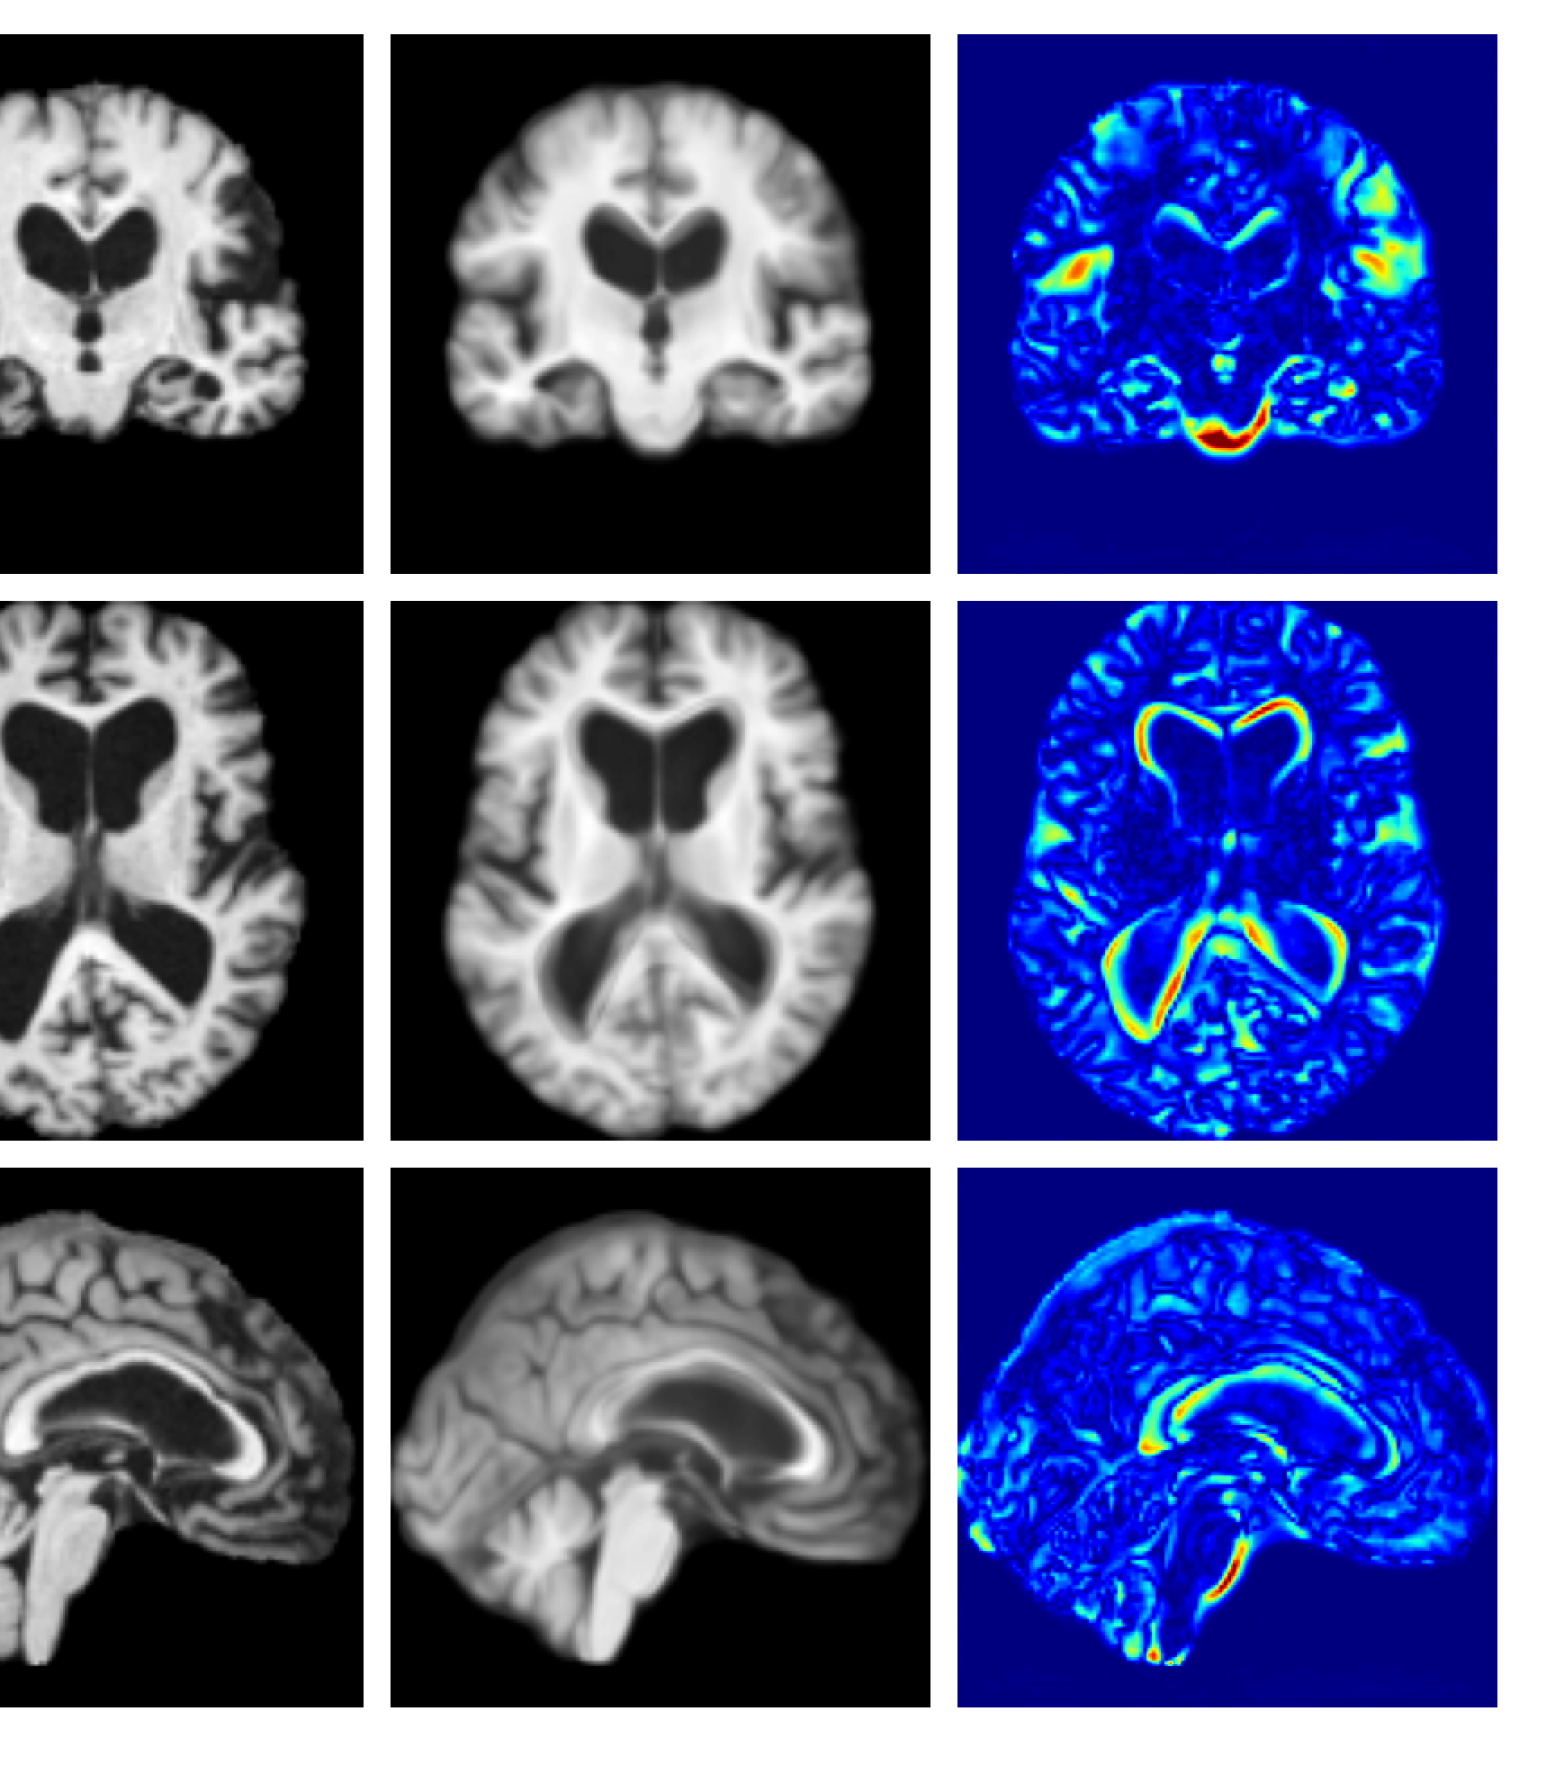

Figure 7 provides example reconstructions and anomaly maps for a healthy subject from the UK Biobank holdout test cohort.

Refer to caption

Figure 7: Example healthy reconstructions and anomaly maps for a sample from the UK Biobank healthy test cohort. For a healthy subject, we should observe no regions highlighted in the anomaly map.